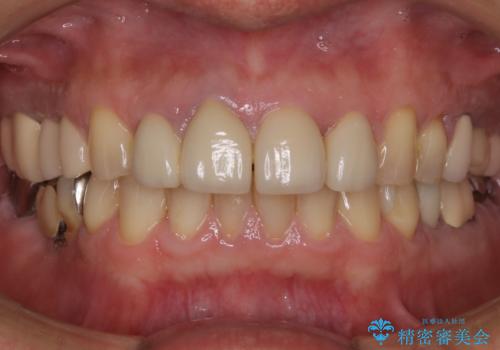

前歯の被せ物をリニューアル

- 上の前歯の正中離開と色味の不満を主訴にご来院されました。

神経を取っている右上2番目の歯は根尖部に病巣があったため根管治療をした上で土台を立て、被せ物の作製を行いました。右上1番目の歯は他院にてとても大きく深い金属の土台が入れられており被せ物の色調に影響を与えていましたが、すべて取りきることのリスクが高いため途中まで除去し目立ちにくいファイバーコアで補強と色調の改善を行いました。